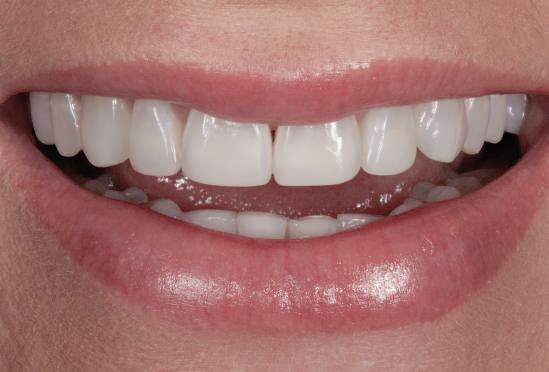

Pentru a maximiza estetica restaurărilor implantare frontale, etapa iniţială a planului de tratament include integrarea protezei în zâmbetul pacientului, în conformitate cu limitările anatomice ale pacientului.

Acest articol examinează rolul bontului în susţinerea succesului estetic şi tehnic. Sunt incluse discuţii cu privire la restaurările cimentate vs fixate cu şurub, selecţia materialului pentru substituţia dintelui frontal şi parametrii designului.

Deşi în acest articol sunt prezentate criteriile pentru fabricarea bontului implantar, este important de menţionat că integrarea zâmbetului pacientului este determinantă înainte de inserarea implantului, iar rolul bontului

în susţinerea esteticii este limitat de procesul de planificare a tratamentului pentru restaurarea finală (fig. 3-5).

Pentru înlocuirea dintelui anterior, selectarea materialului este importantă în succesul estetic, gradul de afişare a dintelui şi gingiei în timpul surâsului având pondere importantă în decizie. S-a demonstrat că în funcţie de grosimea ţesutului care se află deasupra bontului, unul din titan poate crea umbră prin ţesuturile moi. Când grosimea ţesutului era mai mică de 2mm, autorii au arătat că ochiul uman putea detecta reflecţia luminii de pe bontul de titan. Astfel, orice implant plasat vestibular de dinţii adiacenţi sau cu mai puţin de 3mm sub marginea gingivală finală anticipată la un pacient care afişează treimea cervicală a dinţilor în timpul zâmbirii poate necesita un bont de zirconiu. Acest lucru va minimiza umbra situată apical de marginea gingivală, observată în cazul bonturilor de titan. Pacienţii care nu afişează treimea cervicală a dinţilor în cursul zâmbetului larg, permit o mai mare flexibilitate în privinţa alegerii materialului, pentru că riscul reflecţiei date de afişarea metalului este minimă (fig. 11-13). Bonturile de zirconiu reprezintă o opţiune excelentă atunci când accesibilitatea la marginile restaurative este îndoielnică, deoarece permit ca marginile restaurării să fie mai apropiate de marginea gingivală finală, în special în cazurile în care se anticipează recesie gingivală. Dacă există orice retracţie ulterioară, joncţiunea dintre dinte şi restaurare este mai puţin vizibilă şi există o mai mică probabilitate pentru afişarea umbrei în cazul unui bont metalic.

şi pentru a corecta lungimea vizuală a restaurării. Aceasta se poate obţine prin ajustarea nivelului gingival şi a profilului ţesutului moale pe modelul de ţesut moale şi prin fabricarea bontului în conformitate cu acest profil modificat. Totuşi, dacă implantul nu s-a poziţionat la o adâncime de 3-5mm în raport cu marginea gingivală, modificarea nu este posibilă (fig. 11-13).